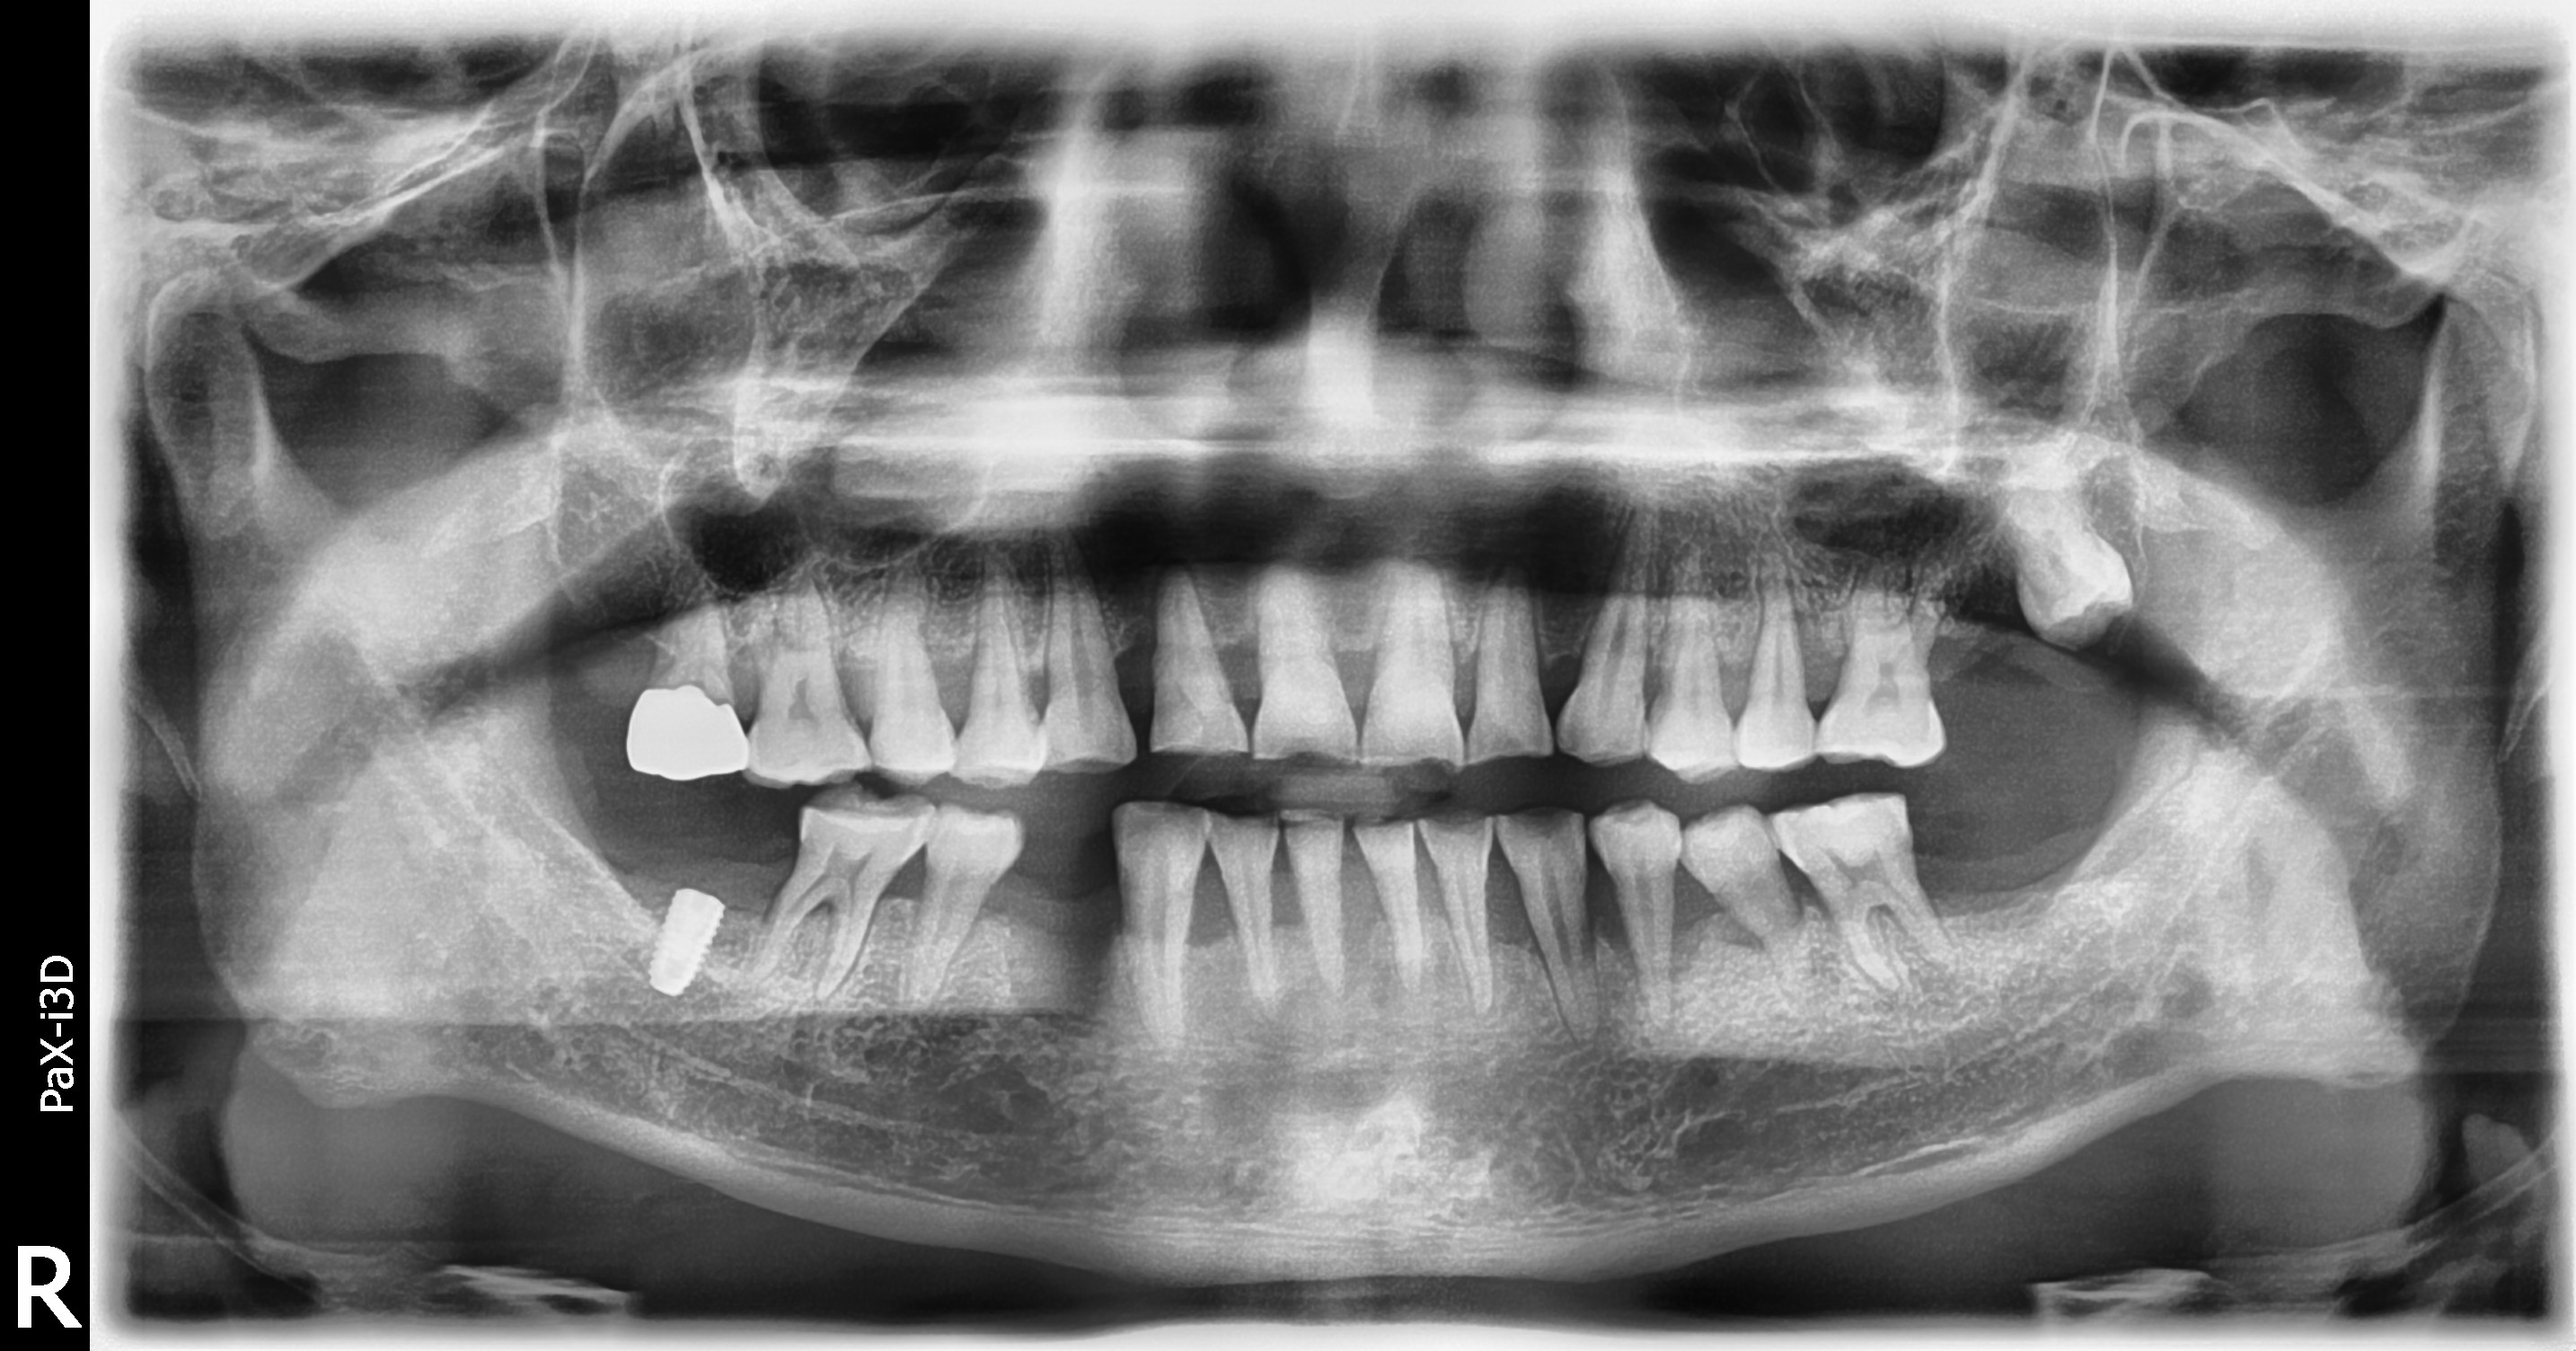

임플란트/틀니